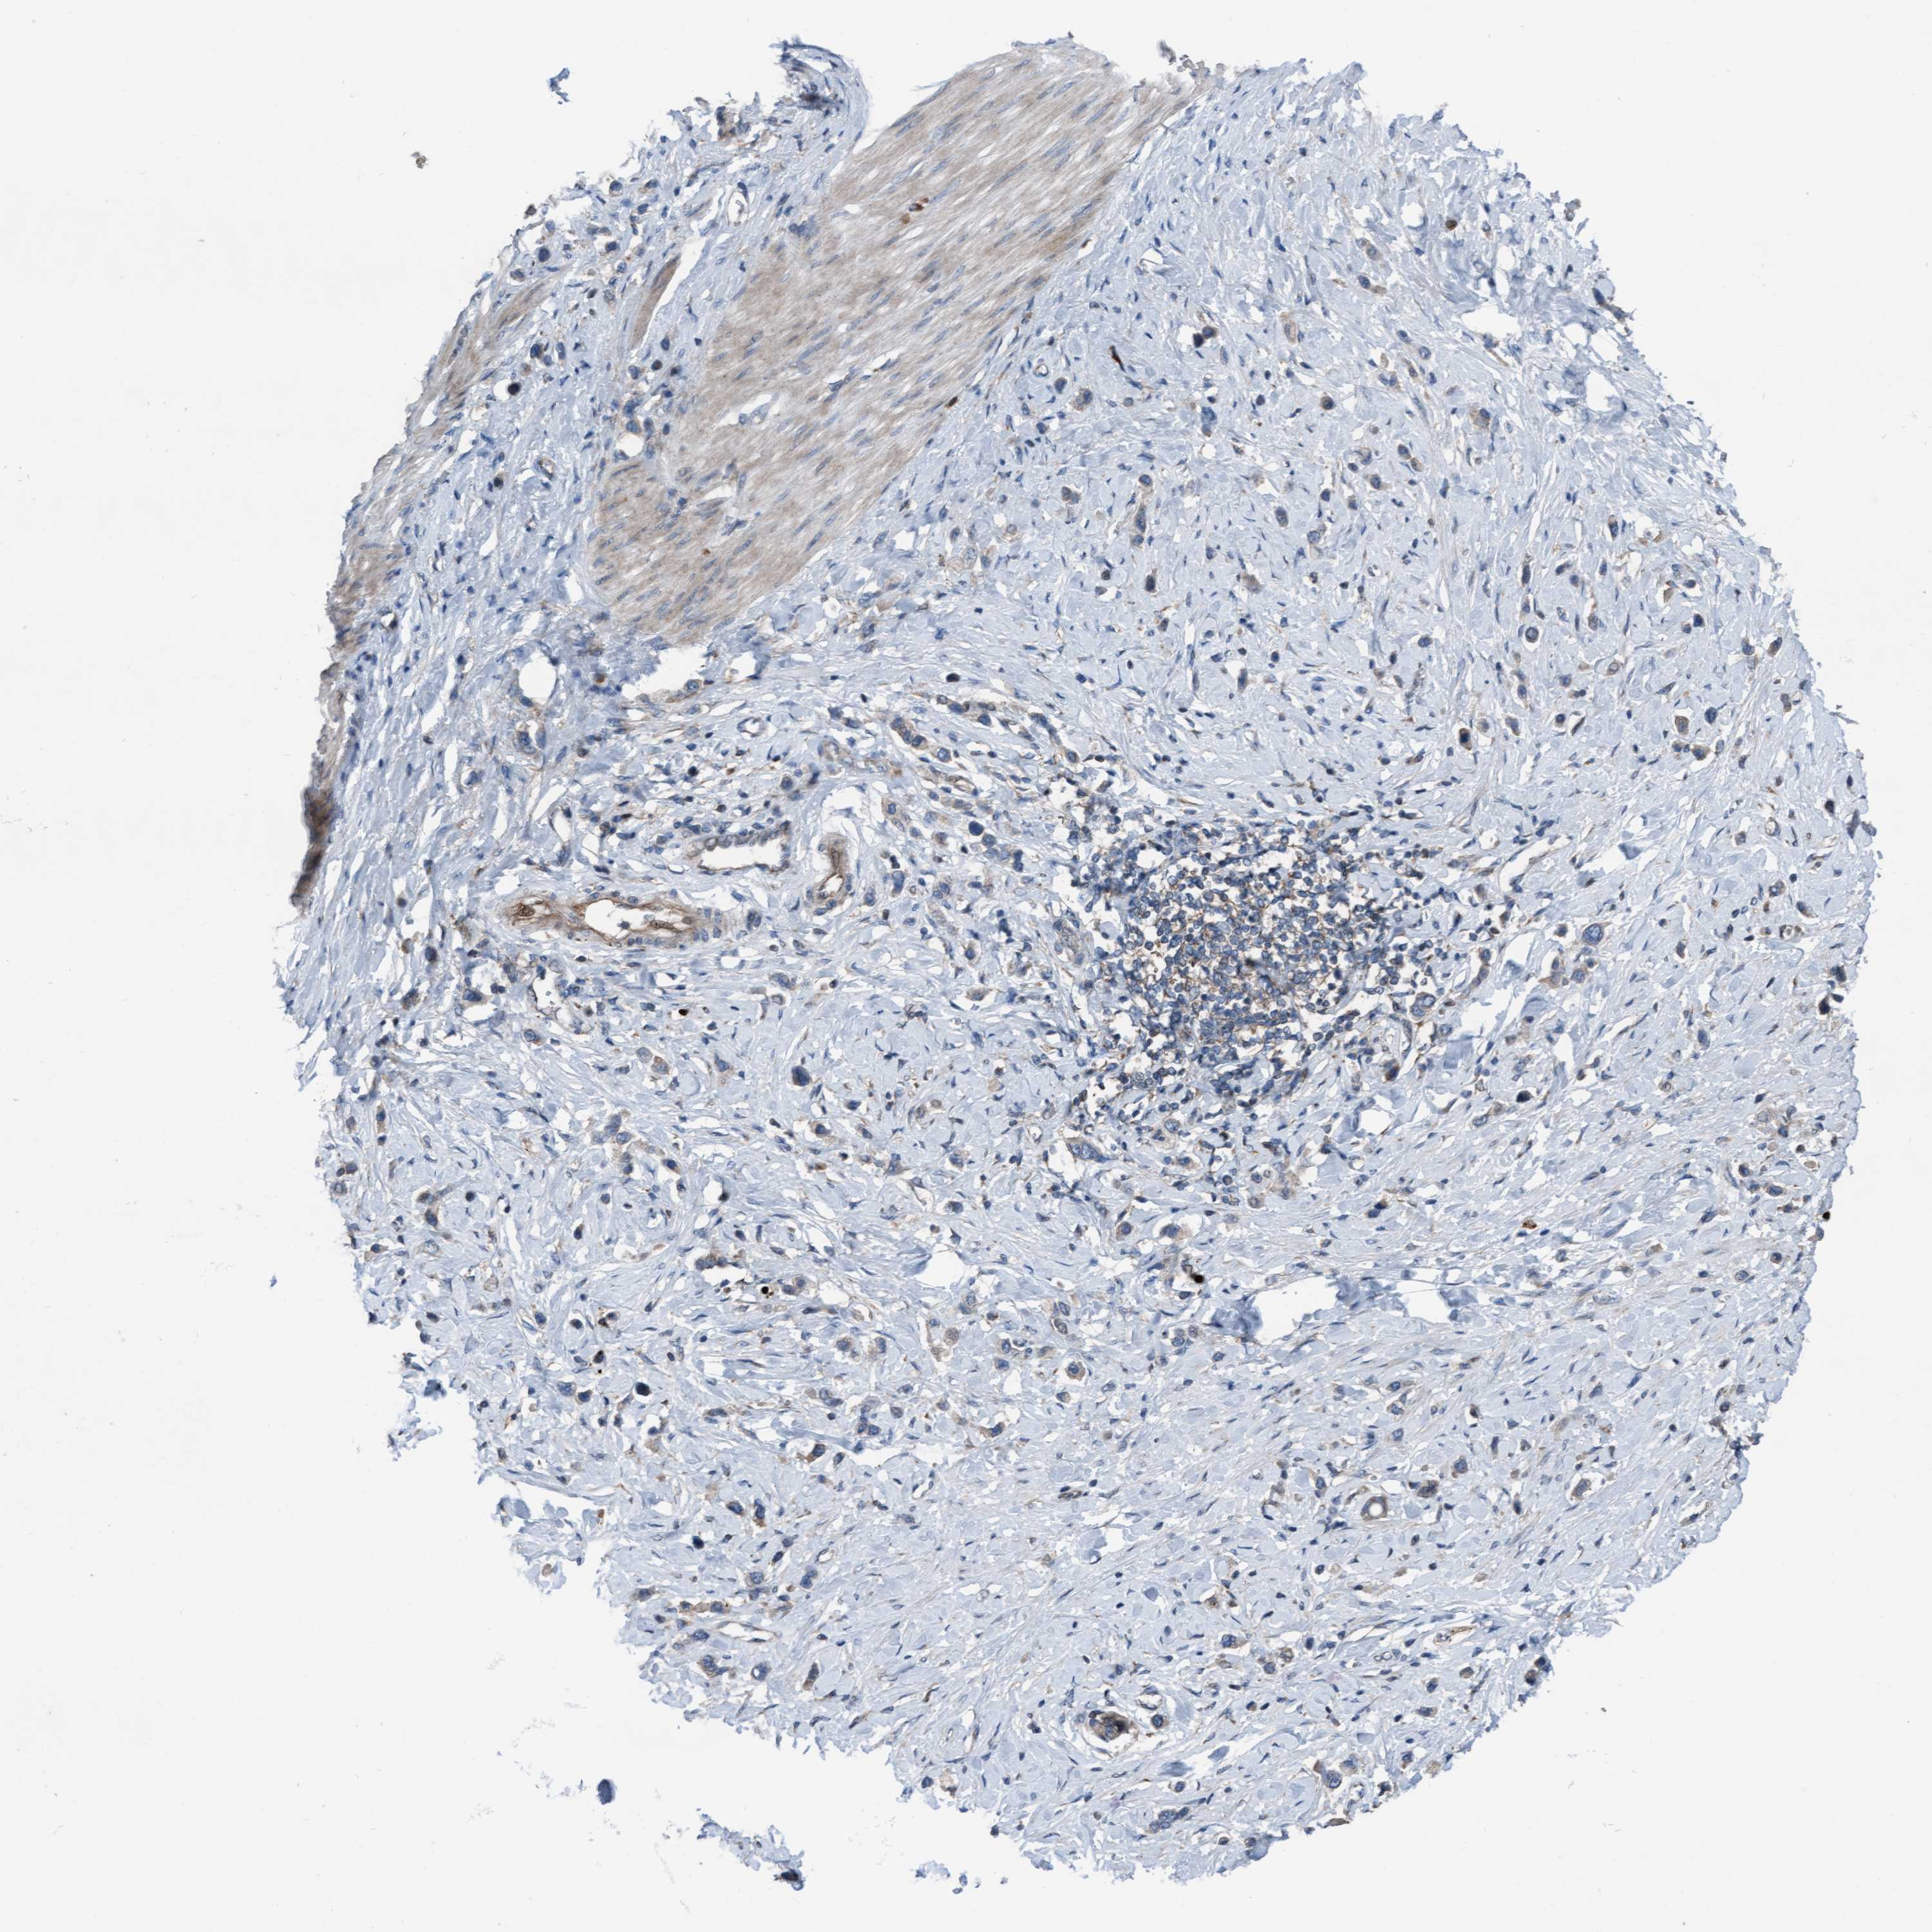

STOMACH CANCER - Protein expressioni

A mouse-over function shows sample information and annotation data. Click on an image to view it in a full screen mode. Samples can be filtered based on level of antibody staining by selecting one or several of the following categories: high, medium, low and not detected. The assay and annotation is described here.

Note that samples used for immunohistochemistry by the Human Protein Atlas do not correspond to samples in the TCGA dataset.

Antibody stainingi

Antibody staining in the annotated cell types in the current human tissue is reported as not detected, low, medium, or high, based on conventional immunohistochemistry profiling in selected tissues. This score is based on the combination of the staining intensity and fraction of stained cells.

Each image is clickable and will lead to virtual microscopy that enables deeper exploration of all samples and also displays staining intensity scores, fraction scores and subcellular localization as well as patient and tissue information for each sample.

Antibody HPA023074

Staining

High

Medium

Low

Not detected

Intensity

Strong

Moderate

Weak

Negative

Quantity

>75%

75%-25%

<25%

None

Location

Nuclear

Cytoplasmic/membranous

Cytoplasmic/membranous,nuclear

Adenocarcinoma, NOS